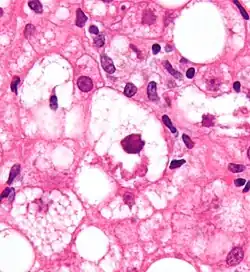

Bei sogenannten Mallory-Körpern handelt es sich um Einschlusskörper in Zellen der Leber, die erstmals von dem amerikanischen Pathologen Frank Burr Mallory (1862–1941) beschrieben wurden.[1] Um den späteren Beitrag des Grazer Pathologen Helmut Denk zu deren weiteren Erforschung zu würdigen, ist auch die Bezeichnung Mallory-Denk-Körper vorgeschlagen worden.[2]

Mallory-Körper treten insbesondere bei der Alkohol-toxischen Hepatitis auf, kommen aber auch bei anderen Erkrankungen der Leber wie zum Beispiel der primären biliären Zirrhose oder dem Morbus Wilson vor. Die an der Bildung beteiligten Mechanismen sind komplex und beinhalten unter anderem eine Proteinfehlfaltung, Veränderungen von Chaperon-Proteinen und eine unverhältnismäßige Expression von Zytokeratinen.[3]